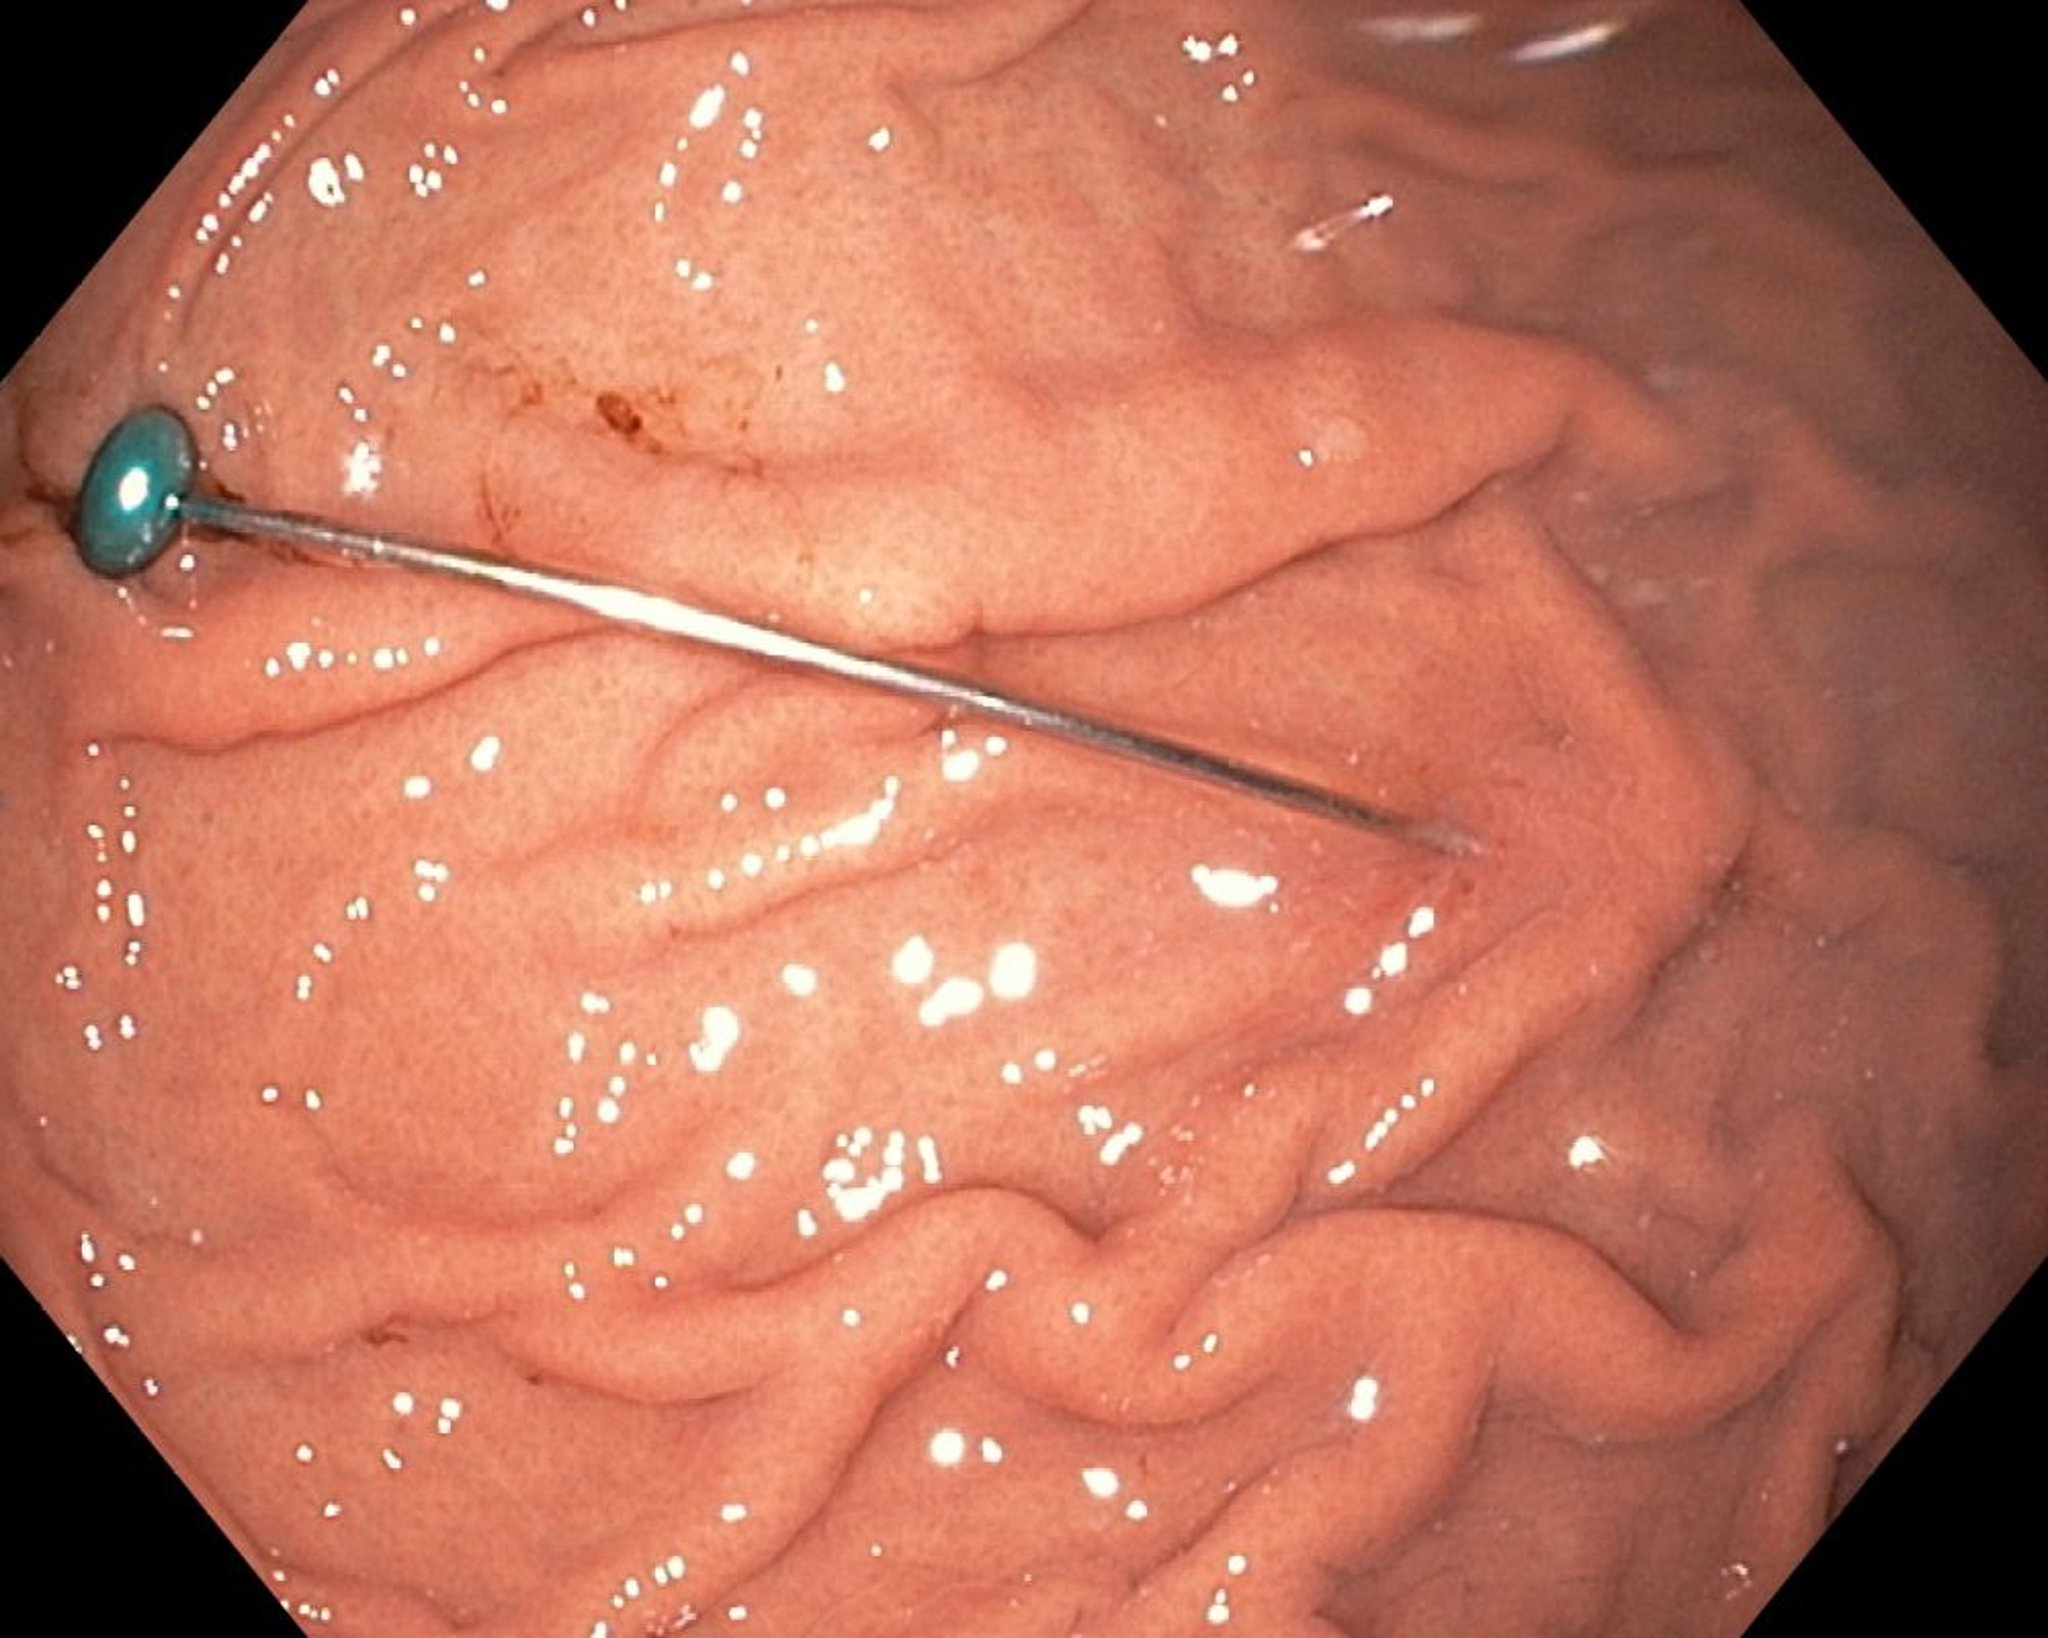

Corpo estraneo nello stomaco (endoscopia)

Questa immagine endoscopica mostra un corpo estraneo affilato nello stomaco.

Immagine fornita da Uday Shankar, MD.